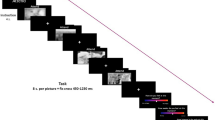

Conditioned Fear Acquisition Task

The acquisition phase of the fear conditioning paradigm used in the present study is illustrated in Fig. 1. The conditioned stimulus (CS) was a visual symbol of lightning (displayed for 200 ms), whereas the unconditioned (aversive) stimulus (UCS) was a moderately painful electrical shock (rated 5–6/10 on the NRS before the study) on the skin of the left lower leg delivered by a concentric electrode with a 0.2-ms constant-current square wave. Half of the CSs were immediately paired with UCS (paired CSs), and the other half were presented alone (unpaired CSs). Furthermore, to ensure participants’ vigilance during the recording, a visual symbol of the sun (displayed for 200 ms) was presented. All participants were asked to report the number of sun symbols at the end of each recording session. Participants who reported a difference of > 2 in the number of sun symbols presented were excluded from further analysis. In each recording session, paired CSs (probability, 45%), unpaired CSs (probability, 45%), and sun symbols (probability, 10%) were presented randomly, and the time interval between conditions was maintained at approximately 5.5–6.5 s.